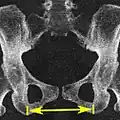

Размеры и форма таза имеют важное значение для родового процесса и подлежат измерению и оценке у всех беременных. Для определения внешних размеров таза у живого человека пользуются измерительным инструментом — тазомером Мартина, внутренние размеры выясняются расчётными методами исходя из внешних, также применяется мануальное исследование через влагалище и ультразвуковые исследования. Рентгенологические исследования, в том числе компьютерная томография, у беременных применяются в исключительных случаях для уточнения в виду нежелательного влияния ионизирующего излучения на плод и красный костный мозг женщины[1].

- Diameter transversa (поперечный диаметр верхней апертуры) — наиболее отдалённое между пограничными линиями — 13,5 (12,8) см

Рентгеновский снимок женского таза в прямой проекции, может использоваться для уточнения размеров таза

Измерение размеров на томограмме низкодозовой компьютерной томографии